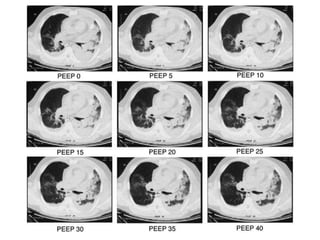

Estrategias ventilatorias El empleo de PEEP aumenta la capacidad residual, ayudando a prevenir el colapso alveolar. Debe incrementarse la PEEP para evitar niveles de  F I O 2  superiores a 0,6. El uso de PEEP > de 12 cm de H 2 O puede asociarse a caída del gasto cardiaco, y debe monitorearse el DO 2 Los intentos por mantener P a CO 2  normales pueden inducir riesgo de volubarotrauma La hipercapnia permisiva puede ser una alternativa

Fuerzas de despegamiento En pulmones alterados las lesiones por “stress de despegamiento”  se relacionan a la apertura y cierre  cíclicos de la pequeña vía aérea, por reclutamiento y desreclutamiento alveolar. La aplicación de PEEP, al aumentar el volumen de fin  de espiración, tiene efecto protectivo. Este efecto sería contrarrestado por el desarrollo de sobredistensión, si es muy alta o no se asocia con VC pequeños

Otros factores de riesgo El incremento de la FR puede aumentar la inflamación por el stress del ciclado, o por la inactivación del surfactante El empleo de altas FiO 2  y la generación de “especies reactivas” del oxígeno pueden producir IPA o distress.  Por ello se aconseja sólo alcanzar FiO 2     90% La TAC de pacientes con distress muestra zonas superiores pequeñas siempre abiertas (baby lung), vastas zonas consolidadas en regiones declives, y zonas intermedias que pueden ser reclutadas/desreclutadas con la VM Por lo anterior, la IPA y el distress son factores importantes de injuria asociada al respirador

Anormalidades del surfactante El aumento de la tensión superficial produce colapso  de la vía aérea distal, con la generación de stress de reapertura Requerimiento de mayores presiones para mantener  abierta la vía aérea Aumento de la presión transpulmonar que favorece la formación de edema La aplicación de PEEP, al evitar el colapso alveolar,  evita la inactivación del surfactante (incluyendo su rol inmunomodulador) ‏

Estrategias preventivas VC de 6ml/Kg teórico Reducción de la presión plateau a menos de 30cmH 2 O Aumento de la PEEP titulada con la curva P/V Maniobras de reclutamiento (en situaciones particulares) ‏

Estrategias ventilatorias Elempleo de PEEP aumenta la capacidad residual, ayudando a prevenir el colapso alveolar. Debe incrementarse la PEEP para evitar niveles de F I O 2 superiores a 0,6. El uso de PEEP > de 12 cm de H 2 O puede asociarse a caída del gasto cardiaco, y debe monitorearse el DO 2 Los intentos por mantener P a CO 2 normales pueden inducir riesgo de volubarotrauma La hipercapnia permisiva puede ser una alternativa

Fuerzas de despegamientoEn pulmones alterados las lesiones por “stress de despegamiento” se relacionan a la apertura y cierre cíclicos de la pequeña vía aérea, por reclutamiento y desreclutamiento alveolar. La aplicación de PEEP, al aumentar el volumen de fin de espiración, tiene efecto protectivo. Este efecto sería contrarrestado por el desarrollo de sobredistensión, si es muy alta o no se asocia con VC pequeños

Otros factores deriesgo El incremento de la FR puede aumentar la inflamación por el stress del ciclado, o por la inactivación del surfactante El empleo de altas FiO 2 y la generación de “especies reactivas” del oxígeno pueden producir IPA o distress. Por ello se aconseja sólo alcanzar FiO 2  90% La TAC de pacientes con distress muestra zonas superiores pequeñas siempre abiertas (baby lung), vastas zonas consolidadas en regiones declives, y zonas intermedias que pueden ser reclutadas/desreclutadas con la VM Por lo anterior, la IPA y el distress son factores importantes de injuria asociada al respirador

Anormalidades del surfactanteEl aumento de la tensión superficial produce colapso de la vía aérea distal, con la generación de stress de reapertura Requerimiento de mayores presiones para mantener abierta la vía aérea Aumento de la presión transpulmonar que favorece la formación de edema La aplicación de PEEP, al evitar el colapso alveolar, evita la inactivación del surfactante (incluyendo su rol inmunomodulador) ‏